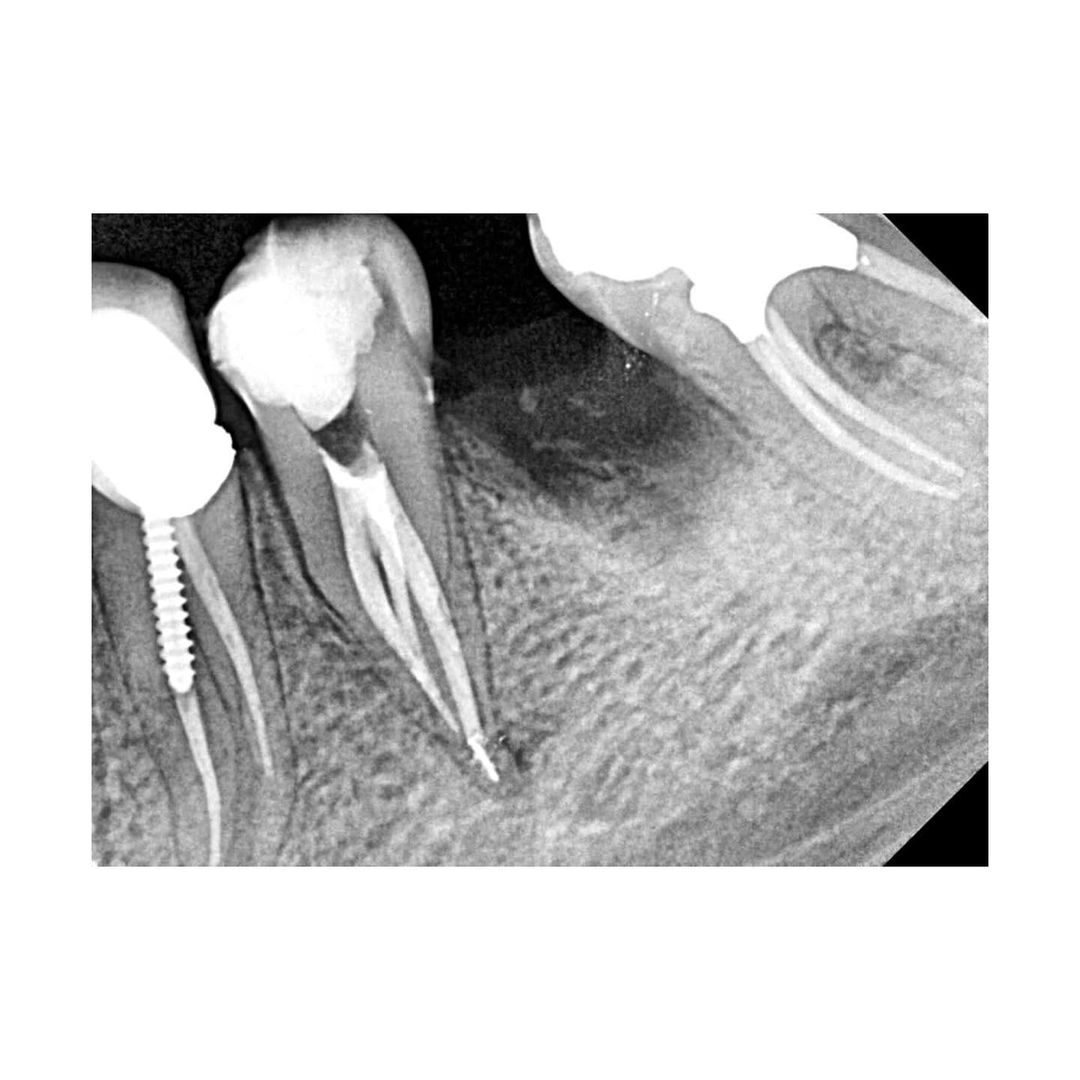

Collection of 3-canal lower premolar.

Collection of 3-canal lower premolar.